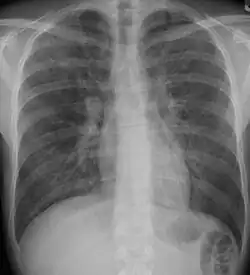

Pneumocystis pneumonia can present with interstitial lung disease, as seen in the reticular markings on this AP chest x-ray.

A chest x-ray is 63% sensitive and 93% specific for ILD.[10] With advances in computed tomography, CT scans of the chest have supplanted lung biopsy as the preferred diagnostic test for ILD. A thoracic CT scan is 91% sensitive and 71% specific for ILD.[10] In higher income countries, less than 10% of people with ILD undergo a lung biopsy as part of the diagnostic evaluation.[16]

Chest radiography is usually the first test to detect interstitial lung diseases, but the chest radiograph can be normal in up to 10% of patients, especially early in the disease process.[19][20]